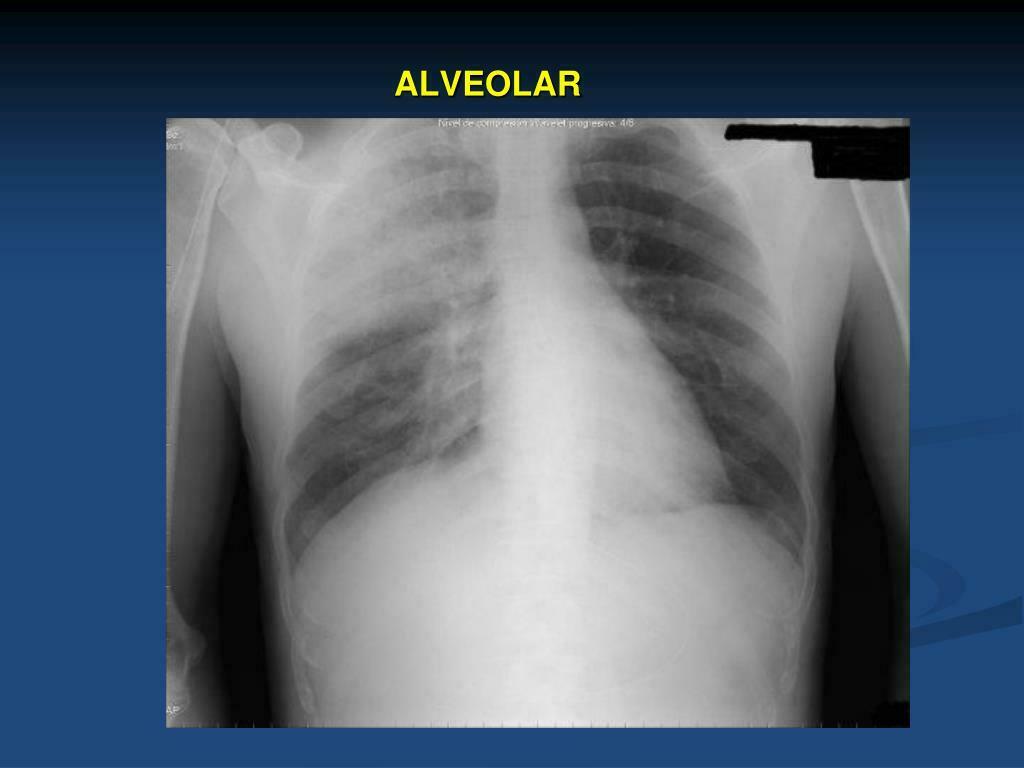

O que esse raio x sugere e quais são as os sinais presentes? Derrame pleural; Imagem em menisco, parabola de Demousiau, opacificação do espaço pleural, deslocamento do diafragma, imagem em menisco, fissuras pleurais e leve deslocamento do mediastino.

Quais são os achados radiológicos do derrame pleural? O que pode causar a doença? -Presença de muito líquido no espaço pleural -Obliteração do seio costofrênico (preenchimento do espaço entre as costelas e o diafragma) -Imagem em menisco -Elevação da cúpula diafragmática -Lawrell pode deslocar o líquido; Tuberculose e neoplasias (Doença pleural), insuficiência cardíaca e congestiva (Doença sistêmica)